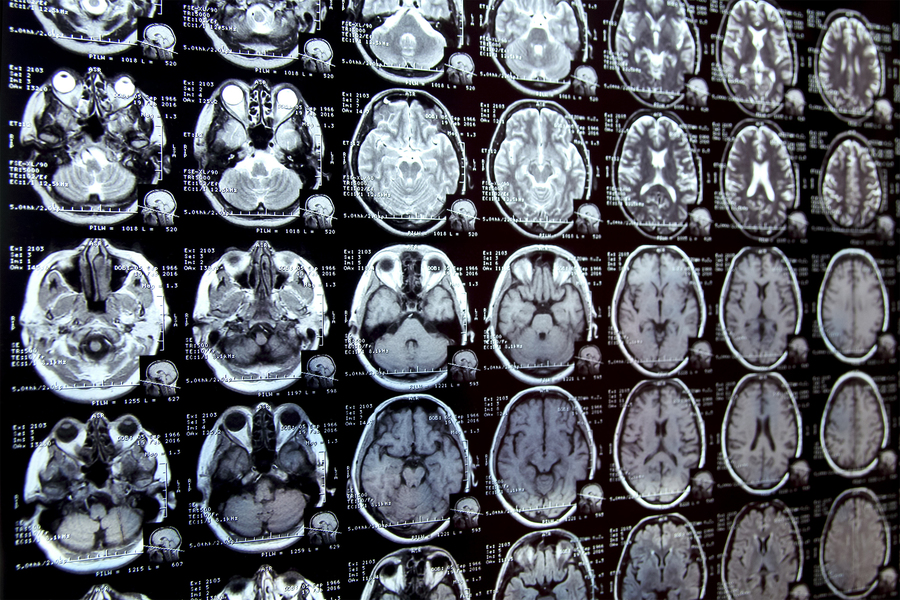

Imagina que necesitas estudiar cómo el hipocampo (una región del cerebro) cambia con la edad. El primer paso es delimitar el hipocampo en una serie de escáneres cerebrales. Esto se conoce como segmentación y, tradicionalmente, es un proceso manual, lento y laborioso. Especialmente cuando las estructuras a estudiar son difíciles de definir.

El nuevo sistema de IA, llamado MultiverSeg, permite a los investigadores segmentar rápidamente conjuntos de datos de imágenes biomédicas. ¿Cómo? Simplemente haciendo clics, dibujando o trazando líneas sobre las imágenes. La IA aprende de estas interacciones y predice la segmentación. Lo más interesante es que, a medida que el usuario anota más imágenes, la cantidad de interacciones necesarias disminuye, ¡llegando incluso a cero!